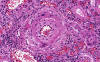

Kidney- Area  3: The blood vessel is replaced by fibrinoid substances.

Kidney- Area  4: In this area, the fibrinoid necrosis extends into the glomerulus.

Kidney- Area  5: A fibrinoid thrombus is presen in this arteriole.

·         Fibrinoid necrosis of arterioles: The blood vessel wall is partially or completely replaced by an eosinophilic granular acellular fibrinoid substance (Kidney- Area 3) which can be demonstrated by special stains or immunohistochemistry. Sometimes the glomeruli may also become necrotic (Kidney- Area 4) and infiltrated by neutrophils and the glomerular blood capillaries may be thrombosed  (Kidney- Area 5). Limited chronic inflammatory cell infiltration may be associated with these vessels.